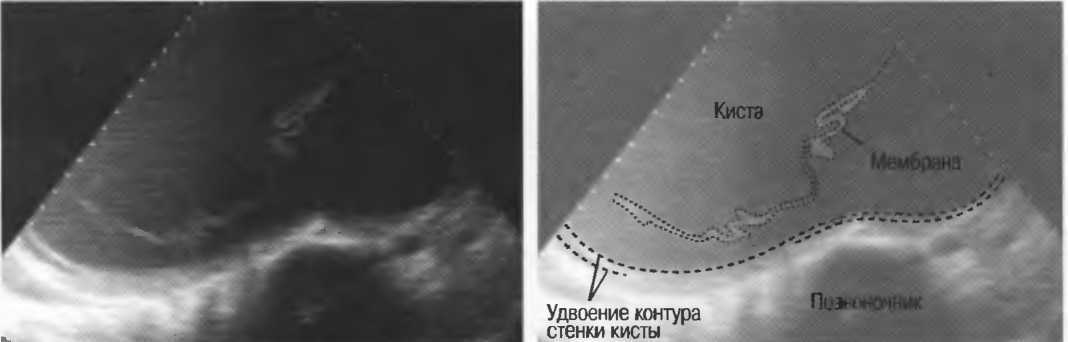

Артефакты могут определяться в любой кистозной структуре (такой, например, как мочевой пузырь или желчный пузырь) и чаще определяются ближе кпереди, становясь менее выраженными на глубине. Они исчезают или меняют свой характер при изменении положения датчика. Но истинные структуры в кисте, такие как перегородки, сохраняют свое местоположение независимо от положения датчика. Истинные отражения имеют место при наличии сгустка крови, гноя, некротической взвеси, и все это чаще визуализируется по задней стенке: если эти структуры не фиксированы к стенке, они изменяют свое положение при перемене положения тела пациента (рис. 16).

Рис. 16а. Злокачественная киста яичника: крупная киста с внутренней перегородкой, которая остается в прежнем положении при сканировании пациентки в различных положениях.

Осадок в кисте может флотировать, формируя уровень, изменяющий свое положение при перемещении пациента (рис. 16б,в).

Рис. 16б. Киста с усилением по задней стенке, латеральными тенями и осадком в полости.

Рис. 16в. Этот же пациент, что и на рис. 16б. Сканирование осуществляется в разных положениях больного. Уровень, создаваемый осадком, смещается.